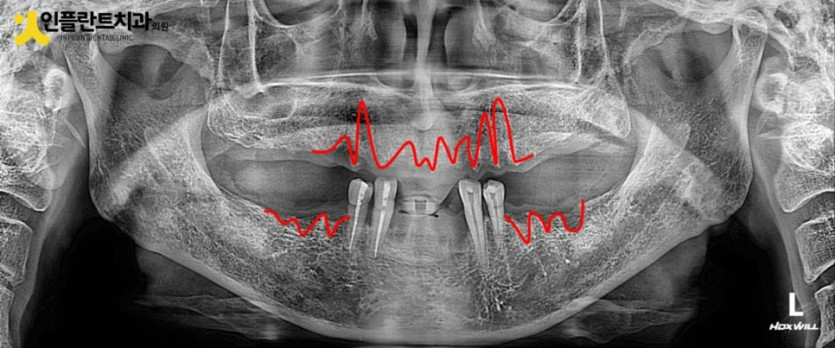

이렇게 발치후 사진을 보시면 이를 뽑은 흔적을 살펴보실 수 있는데요

발치를 하고 나면 그 부위의 뼈가 본연의 역할이 끝나서 흡수되고 부분적으로 차오르는데 최소 3개월 이상의 시간이 소요됩니다.

잇몸뼈는 세월의 흐름에 따라 지속적으로 변하는데 특히 발치 후 이 시기에 많은 변화가 있기 때문에

최종틀니는 필요시 충분한 시간을 지난 후에 제작하시는게 좋습니다.